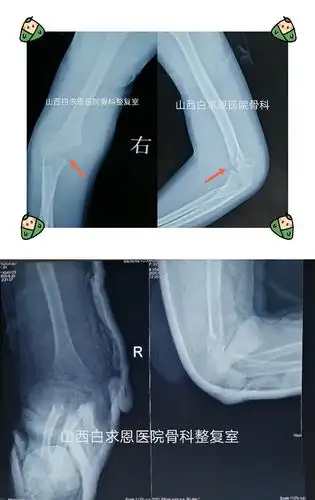

女孩,6岁,右肱骨髁上骨折